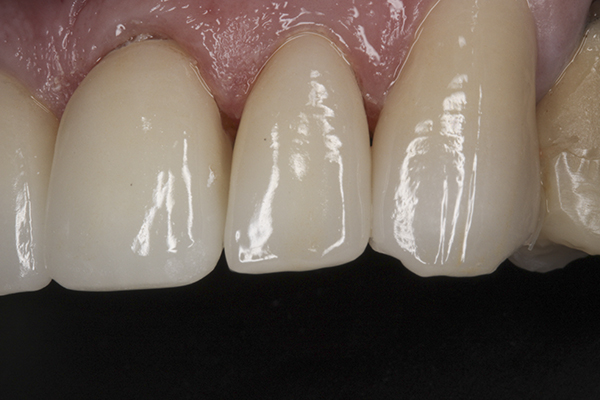

(39.) Postoperative anterior, close-up view.

Figure 39

Based on examination of the mounted models, it was decided to treat the patient in centric relation and an additive equilibration approach was used to idealize the planes of occlusion. On the articulator, the patient’s first point of contact in centric relation was the starting point and an additive equilibration technique was implemented, building the teeth to meet ideally at the patient’s first point of contact. A diagnostic wax-up was completed on the mounted models to determine where the anterior and posterior teeth needed to be in space. A template from the wax-up was used to fabricate the anterior provisional restorations. The anterior teeth were restored with full-coverage restorations, creating ideal stops between the lower incisal edges and upper cingulums. The maxillary incisal edges were placed to provide proper phonetics and an acceptable esthetic outcome, while still working within the envelope of function. All of these parameters are worked out in the provisionals prior to moving forward with definitive restorations. With the anterior provisionals in place, posterior composite tops were bonded to his existing dentition, creating ideal centric stops on the posterior teeth. The anterior and canine guidance was developed, resulting in immediate separation of the posterior teeth during all excursive movements (Figure 17 through Figure 28). Once the author and patient were happy with the function, esthetics, phonetics, and comfort of the provisionals, an impression of the approved provisionals was taken and sent to the laboratory to use as a guide in the fabrication of the final anterior crowns. With the final restorations delivered, the patient was extremely happy with his new smile. Most importantly, proper anterior and canine guidance in harmony with his envelope of function was achieved, which resulted in comfortable function and immediate separation of the posterior teeth during protrusive and lateral excursions (Figure 29 through Figure 42).